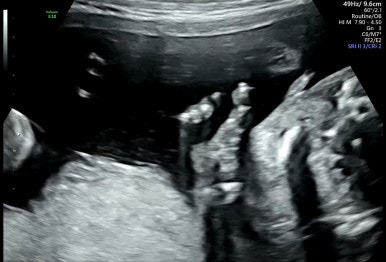

28주 1일

입체초음파로 태아의 얼굴을 볼 수 있는 시기이다!

제일 기다렸던 때이고, 다행히 태아 얼굴을 볼 수 있었다.